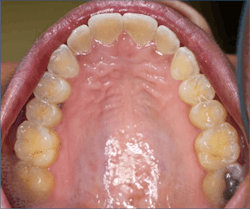

Dental erosion is a chemical process characterized by acid dissolution of dental hard tissue resulting in an irreversible loss of tooth structure. Acid destruction of the dentition occurs with both extrinsic and intrinsic factors. Extrinsic factors are caused by bacteria that produce acidic byproducts in persons that have diets high in sucrose and poor oral hygiene, or diets that are high in acidity. Intrinsic factors such as acid reflux or the purging associated with BN are also causative effects.5 Perimolysis is a specific form of tooth erosion that’s caused from intrinsic factors without bacterial involvement6 (figures 1,2).

Dental patients with eating disorders may also present as physically healthy and be considered ASA I patients. Therefore, it is prudent for practicing dental hygienists and dentists to be familiar with the oral manifestations of eating disorders so that they can recognize the oral signs of an eating disorder and refer the patient for proper treatment.2,3,5,8 Particularly, identification of the early signs of periomolysis before more enamel is lost as seen in Figures 1, and 2 is considered optimal.